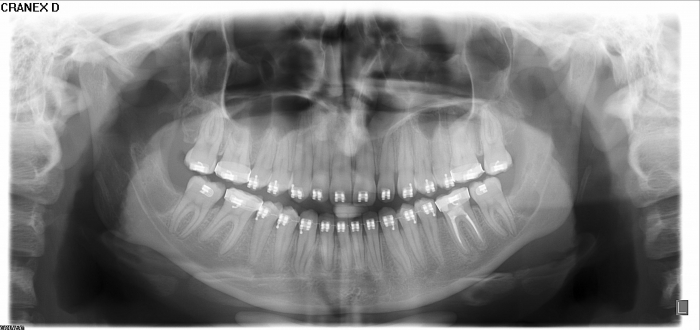

Rx Panoramico inicial - Clínica Cliniface

Rx Panoramico inicial